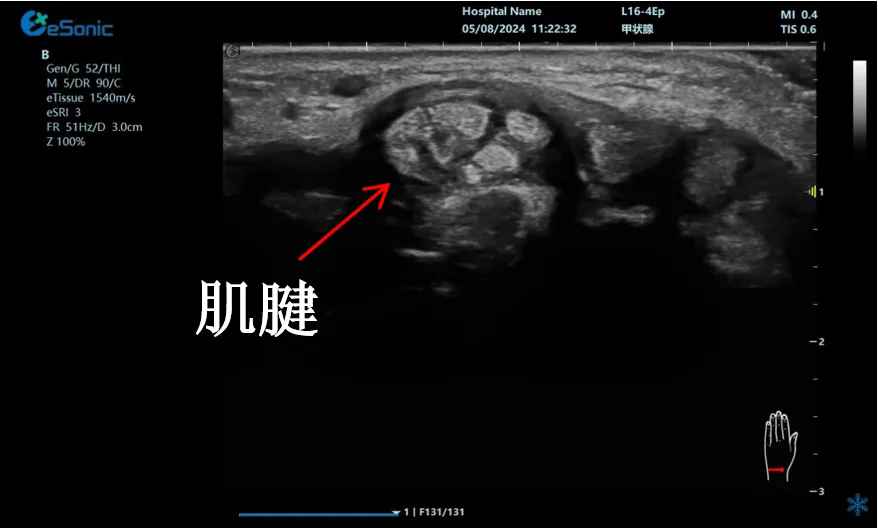

mFlow?技术在腱鞘炎诊疗中的应用

【背景】:左手腕关节第四腔室腱鞘炎。

【痛点】:普通彩色多普勒不敏感,只能看到细小点状血流,容易被忽略,难以进行分级诊断和疗效评估。

【方案】:百乐博平台医疗(ESI)超微血流技术可以看到腔室内肌腱周围环状血流,可充分提示:

1、处于炎症活动期;

2、根据血流进行分级诊断提示1级;

3、治疗后根据血流多少评估疗效(见右下图:治疗10天后复查超声,微血流图像血供消失)。